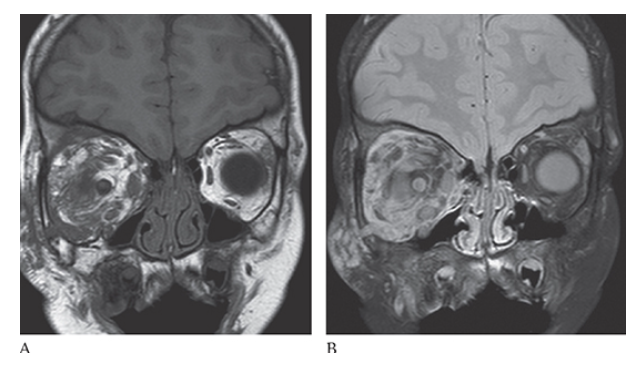

What is A

Neurofibromatosis (NF1). Coronal T1W image shows low-signal-intensity mass within the right orbit which is bright on T2W images

What is B

Neurofibromatosis (NF1). Coronal T1W image consistent with a plexiform neurofibroma.